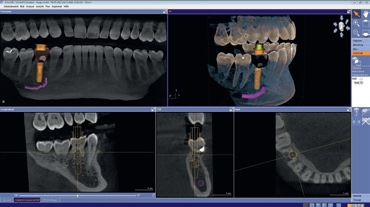

Zur optimalen Behandlungsplanung wurde neben dem DVT ein intraoraler Scan mit der CEREC Omnicam durchgeführt. Die vorhandenen Daten wurden sodann im Implantatplanungsprogramm (Galileos Implant, Dentsply Sirona) für die prothetische Planung sowie für das Design einer Bohrschablone mittels der CERECSoftware vorgenommen und zusammengeführt. Die Fertigung der Bohrschablone erfolgte binnen 45 Minuten direkt in der Praxis mit der Schleifeinheit CEREC MC XL Premium Package. Anschließend wurde die Titanhülse für die geführte Insertion eingeklebt (Abb. 4 bis 6).

Die intraorale Röntgenaufnahme zeigte die übliche 2-wurzelige Konfiguration des Milchmolaren, apikal das Foramen mentale sowie gering ausgeprägte trabekuläre Strukturen der regionalen Spongiosa aufgrund der kurzen Wurzelkonfiguration (Abb. 2). Eine geführte Implantation, für deren Umsetzung ein DVT angefertigt wurde (Orthophos XG 3D), bot hier den Vorteil einer sicheren Führung ohne Richtungsablenkung durch die bestehenden Alveolen sowie der optimalen Ausnutzung des vorhandenen Raumangebots, um maximale Stabilität zu erreichen. Aufgrund der größeren mesiodistalen Breite des Zahnes 85 im Vergleich zu üblichen Prämolaren orientierte ich mich bei der prothetischen Planung am vorhandenen Milchmolaren.